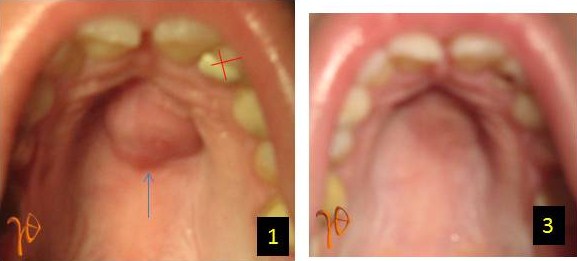

Οι πιο συχνές βλάβες στο στόμα είναι τα αποστήματα, τα οποία όταν οφείλονται σε μικροβιακές λοιμώξεις δοντιών της άνω γνάθου μπορούν να εκδηλώνονται και στην υπερώα (Εικόνα 3). Η θεραπεία τους προϋποθέτει την θεραπεία του υπεύθυνου δοντιού.

Εικόνα 3. α. Απόστημα που οφείλεται σε γομφίο οδόντα (βέλος), β. Απόστημα που οφείλεται σε τομέα οδόντα (βέλος).